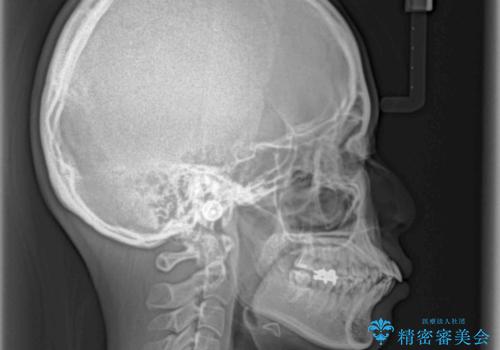

- 口元の突出感と口の閉じにくさを気にして来院された患者様です。

上下左右第一小臼歯4本を抜歯し、ワイヤー装置にて口元を引っ込めるよう矯正治療を行うこととしました。